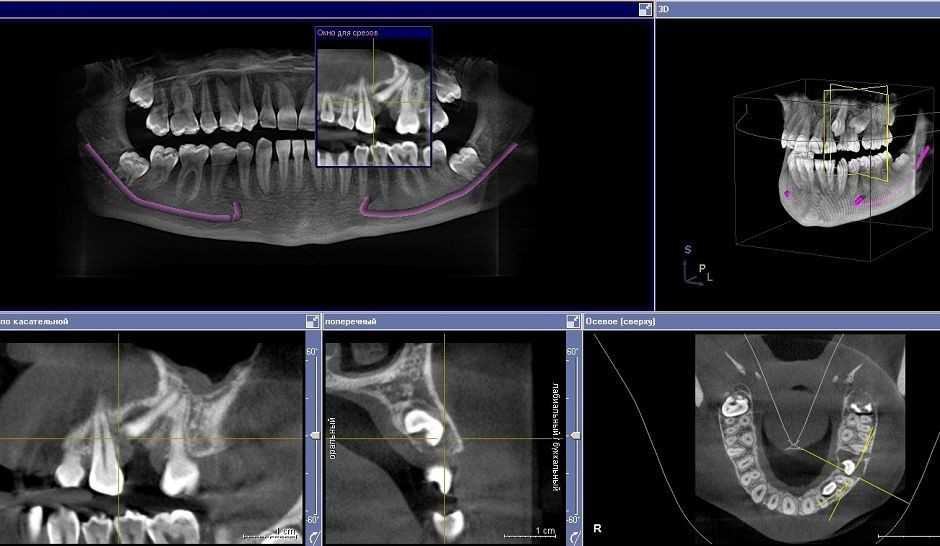

Кт зуба рядом

Кт зуба рядом 109 фотографий